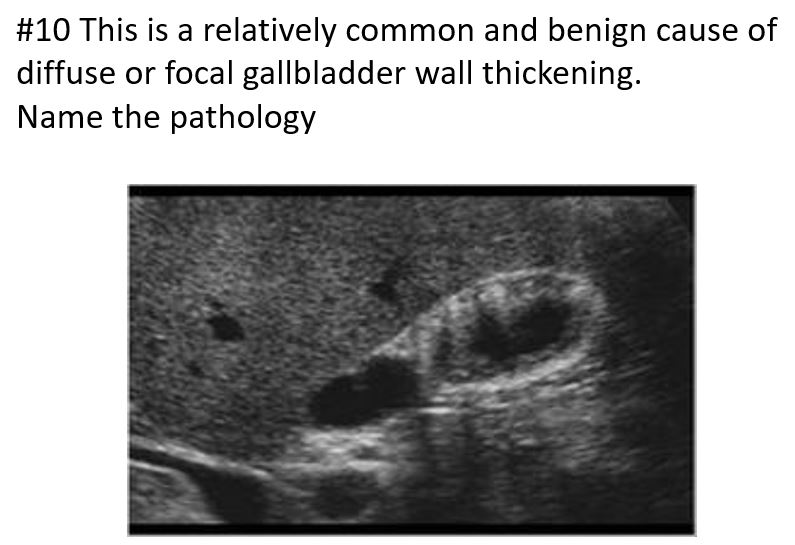

Benign condition that involves a hyperplastic change in the gallbladder wall.

Exaggeration of normal invaginations of the luminal epithelium (called Rokitansky-Aschoff sinuses)

Cholesterol Crystals, Mucosal Hyperplasia, Muscular Thickening, Papillomas

The lesion remains immobile

No Acoustic Shadow

Artifact: comet tail

Adenomyomatosis

Adenomyomatosis

artifact: comet tail